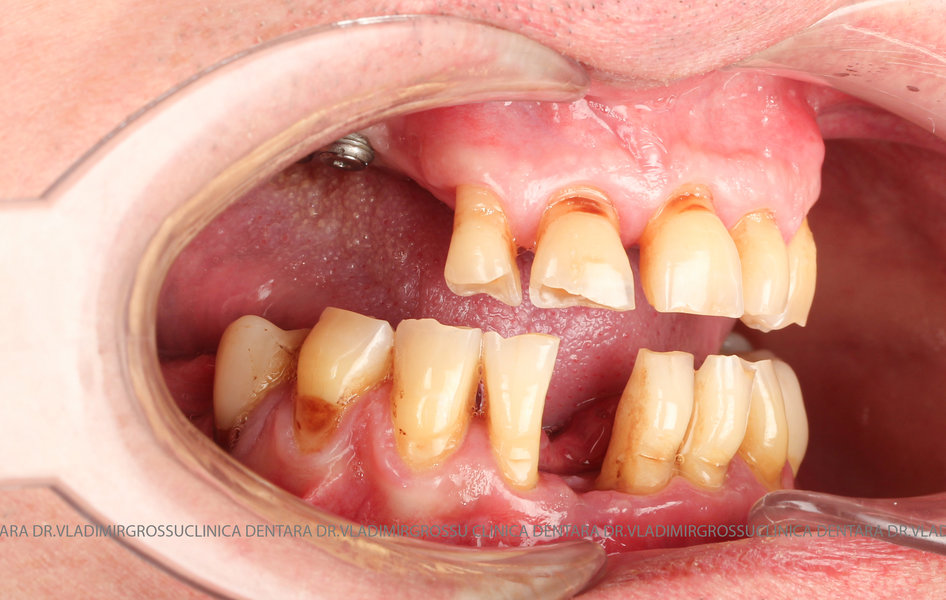

Cazuri clinice conceptul All-on-6